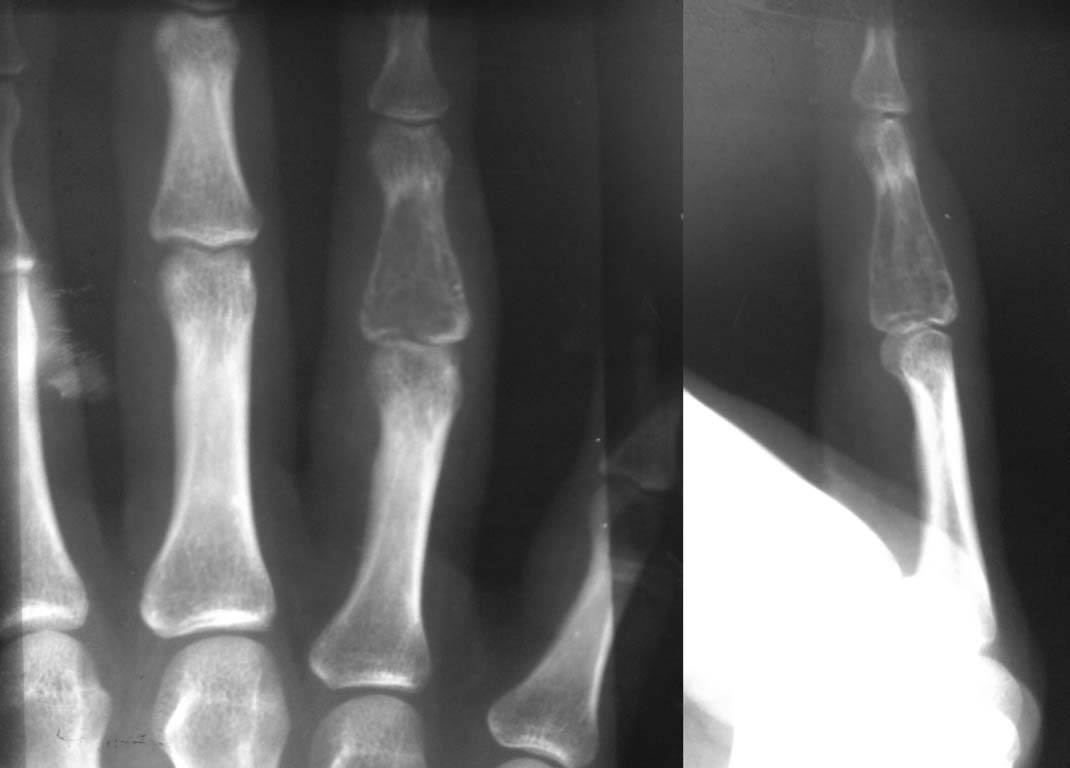

Больная 32 года.  Находилась на лечении в отделении микрохирургии  кисти г. Хабаровск  с  20.09.11 по 30.09.11  с диагнозом – энхондрома  основания средней фаланги  4 пальца левой кисти, патологический перелом   основания средней фаланги. 23.09.11 – операция – резекция опухоли, аллопластика Chronos.  По данным гистологического обследования – гигантоклеточная опухоль. Дальнейшее лечение – 5 недель иммобилизации.  В течении полугода – не наблюдалась.

Повторное обращение в марте  2012 года – жалобы на выраженный отек  4 пальца, нарушение функции.  На R-n – перестройки   Chronos не произошло,  тотальный лизис  средней фаланги.  Госпитализирована с диагнозом остеобластокластома  средней фаланги  4 пальца левой кисти, литическая форма.  06.03.12 – операция, удаление Chronos, резекция  опухоли, наложение конструкции из спиц. Во время операции – от средней фаланги осталась только резко истонченная головка.

Наша тактика – в течение нескольких месяцев наблюдаем, R-n контроль. Если рост опухоли прекратится, проводим костную аутопластику средней фаланги или  дистракционное удлинение проксимальной фаланги с последующим эндопротезированием сустава.

Если распространение опухоли продолжится – ампутация до здоровых тканей.